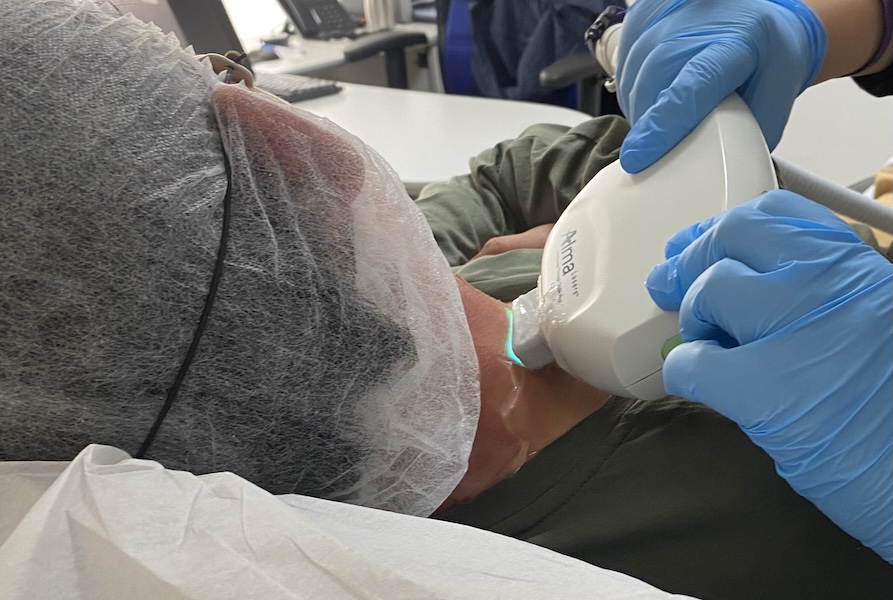

SERVICIO MÉDICO CIRUGÍA VASCULAR

- Especialistas en cirugía vascular y dermatología láser.

- Procedimientos seguros, eficaces y ambulatorios.